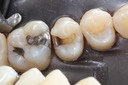

Larry Fujioka #20-21 caries removal